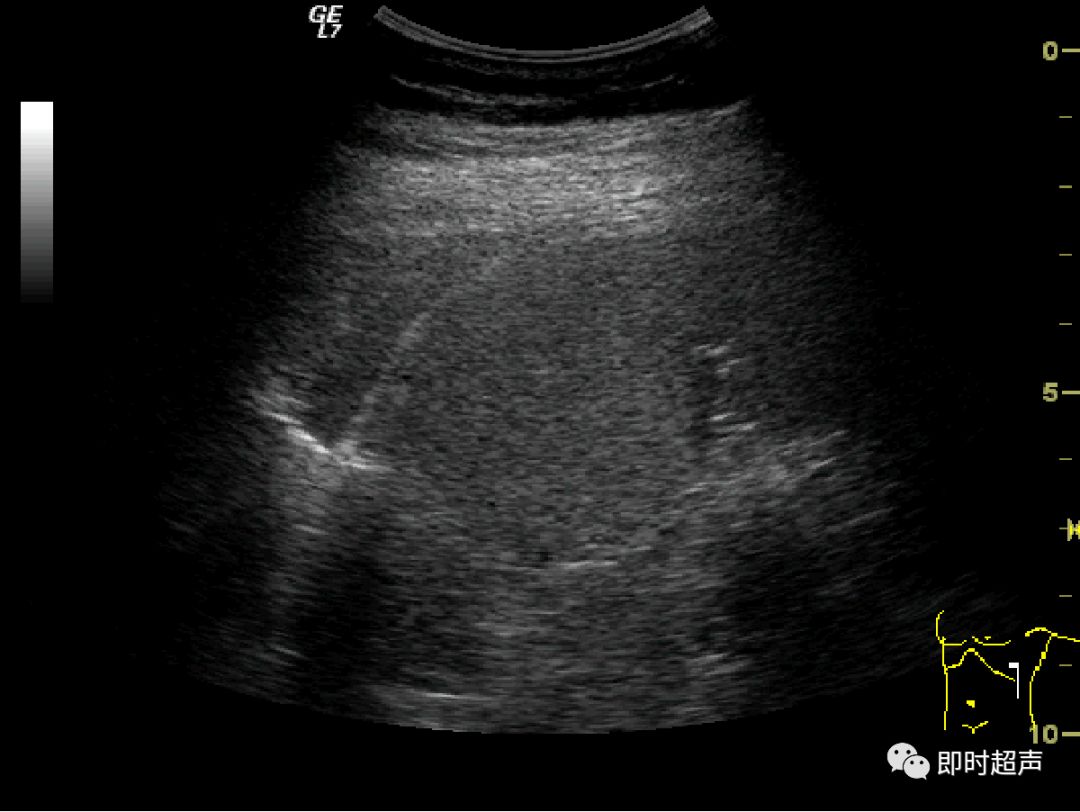

内脏反转超声报告

内脏反转超声报告,内脏反位超声报告模板